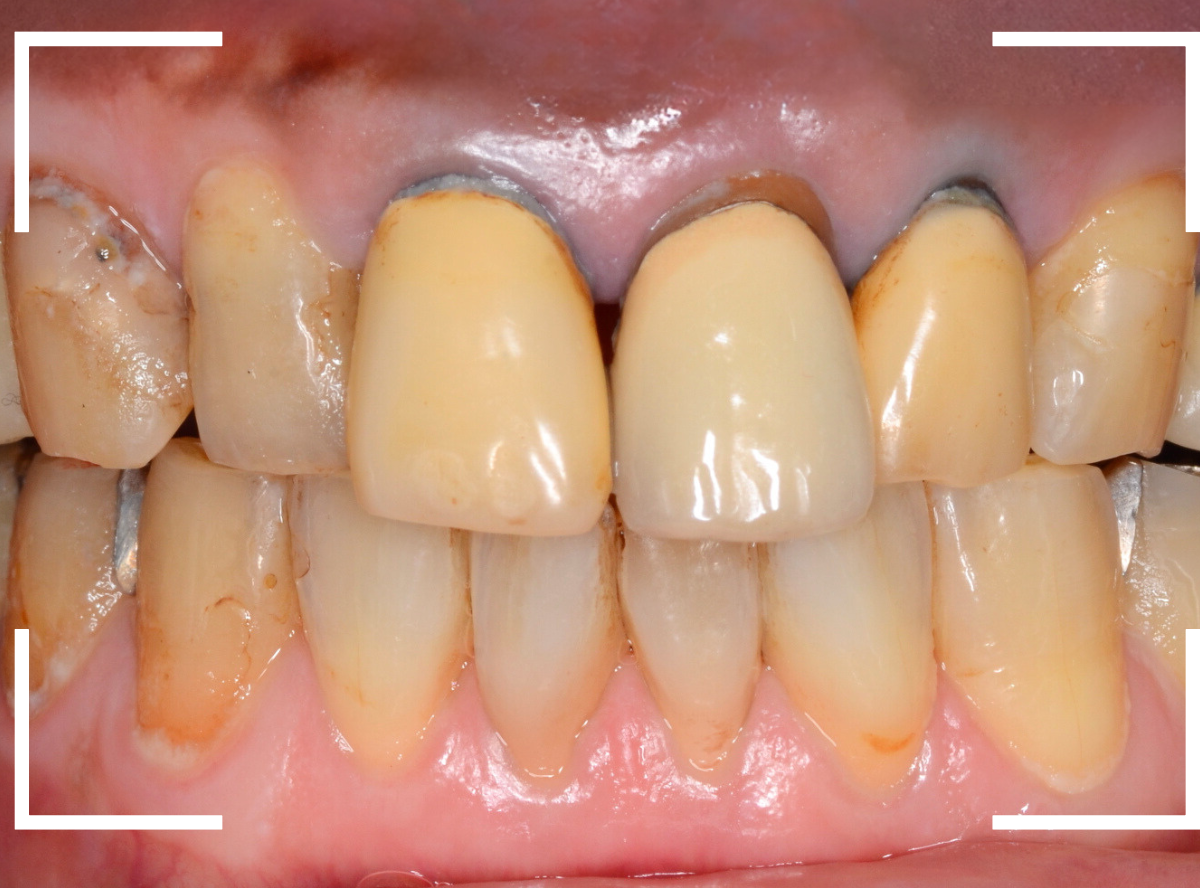

今回は、前歯のさし歯が古くなったので、セラミックで綺麗にしたいというご希望の患者さんです。

患者さんのご希望は白い〇部分の3本でしたが、レントゲン検査をすると隣の2本も虫歯があり、一緒に治療をする事になりました。

左側の2本は虫歯を除去してみないと最終的にどのようにお治しするか何とも言えない状況でしたので、同時に治療しながら最終的な仕上げはご相談、となりました。

まず、前歯のさし歯を外します。

神経を取っている歯(無髄歯)ですので、痛みはありませんが、前後の2本は虫歯になっています。

これら、歯全体を覆うさし歯の中の虫歯はレントゲン写真でも写ってこないため、治療前に正確な判断ができません。

治療前後の写真です。

やはり、上の前歯は大きく印象が変わりますね。